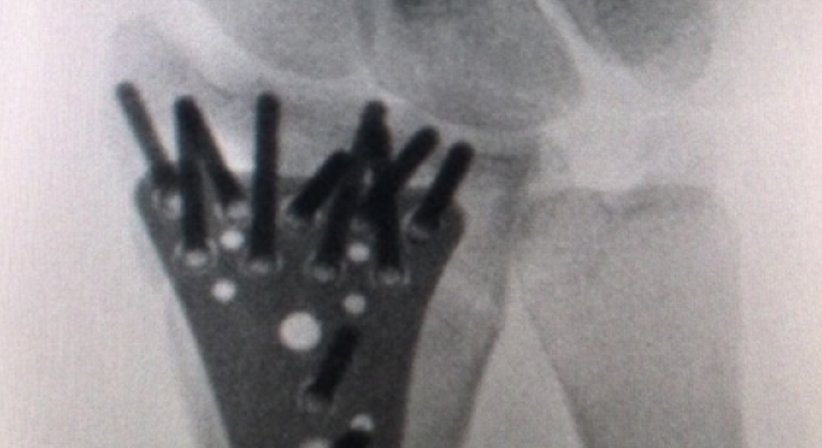

Versorgung von Knochenbrüchen

Osteosynthesen - OA Dr. Andreas Mondl - Unfallchirurg Wien 1220